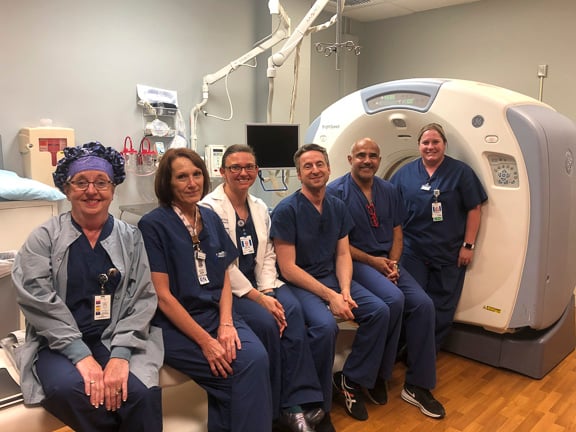

Dr. Massari, a member of the UMass Neurointerventional Radiology Group performed a transpedicular lumbar vertebra biopsy on a patient referred by a local practitioner. Pictured is the radiology team from left to right: Lisa Laprade, procedural technician, Jayne Roose, RN, Kalyn Dhroso, PA, Francesco Massari MD, Amin Chaoui, MD, Danielle McHugh RT CT.